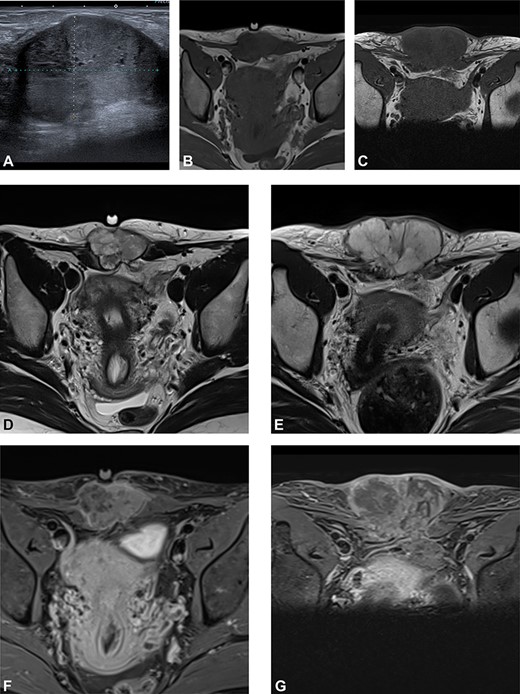

(A) Preoperative ultrasound: ultrasound exam at diagnosis showing a well-defined mass with acoustic enhancement and diffuse ground-glass echoes. (B) Magnetic resonance imaging (MRI) findings: before neoadjuvant radiotherapy (B, D, F) and at the end of the treatment (C, E, G). MRI exams show a well-defined solid mass which presents iso-signal on T1WI (B, C), hyper signal on T2WI (D, E) and heterogeneous enhancement after gadolinium injection (F, G). This mass partially involves both rectus abdominis muscles. A progression, mainly due to necrosis, with an increased size after radiotherapy can be observed.

We present the case of a 44-year-old woman with no previous history of endometriosis, cancer or other relevant medical condition. She had two cesarean deliveries by a Pfannenstiel incision in 2004 and 2014. In May 2018, the patient presented a subcutaneous abdominal wall mass. The ultrasound described a 2-cm nodule compatible with an endometrioma developed on cesarean section scar. From January 2019, the patient reported a rapidly growing and painful mass, and the abdominal ultrasound confirmed a 45-mm well-defined mass showing acoustic enhancement with diffuse ground-glass echoes (Fig. 1A). The pelvic magnetic resonance imaging (MRI) confirmed an infiltrative heterogeneous lesion measuring 5 cm arising from the Pfannenstiel incision and partially involving rectus abdominis muscles (Fig. 1B,D,F). The MRI did not evidence other signs of pelvic or extra-pelvic endometriosis. The patient was referred to our comprehensive cancer center. Physical examination revealed an abdominal wall mass on the cesarean section scar, measuring around 6 cm (Fig. 2A). No abnormal findings were observed in pelvic examination. The ultrasound-guided biopsy revealed a clear cell carcinoma. Microscopic examination showed a malignant proliferation with glandular, nested and focal papillary patterns. Tumor cells had clear cytoplasm, with hyperchromatic nuclei and hobnail feature (Fig. 3I-A,B,C). They were strongly immunoreactive for CK7, PAX8 and HNF-1β (Fig. 3I-D,E). They were negative for calretinin, CK20, CK5/6, WT1, ER and PR. There was a wild-type pattern with anti-p53 antibody (weak and heterogeneous positivity) (Fig. 3I-F). A hysteroscopy and curettage showed a normal endometrium. Computed tomography of the chest, abdomen and pelvis did not evidence distant metastasis. After discussion at the tumor board, neoadjuvant radiation therapy before surgical excision was recommended due to rapid and extensive local progression. From March 2019 to May 2019, 50 Gy was delivered in 25 fractions to the abdominal wall tumor with helicoidal intensity-modulated radiation therapy (IMRT) using Tomotherapy® (Fig. 4). We tried to spare the right ovary from the irradiation fields, delivering a maximum dose of 5 Gy and a mean dose of 3.9 Gy. In June 2019, a wide surgical excision of the lesion (Fig. 3II) and abdominal wall reconstruction using a biological mesh, as well as total hysterectomy and bilateral salpingectomy, were performed. A careful inspection of abdominopelvic cavity was done during surgery, and no signs of endometriosis were found. Both ovaries were macroscopically normal.